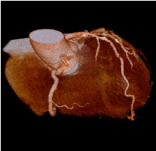

心臓冠動脈VR -

心臓冠動脈MIP -

64列マルチスライスCTにより高速スキャンが可能になったことで心臓など動きの早い臓器の検査もできるようになりました。

今までは入院して血管からカテーテルという管を挿入して検査をしなければならなかった情報を外来で一回の造影CT検査で得ることができます。(入院の必要はありません)

CTで撮影した心臓の血管の立体像です。 -

左と同じ患者様です。(真ん中に狭い血管が見つかりました) -